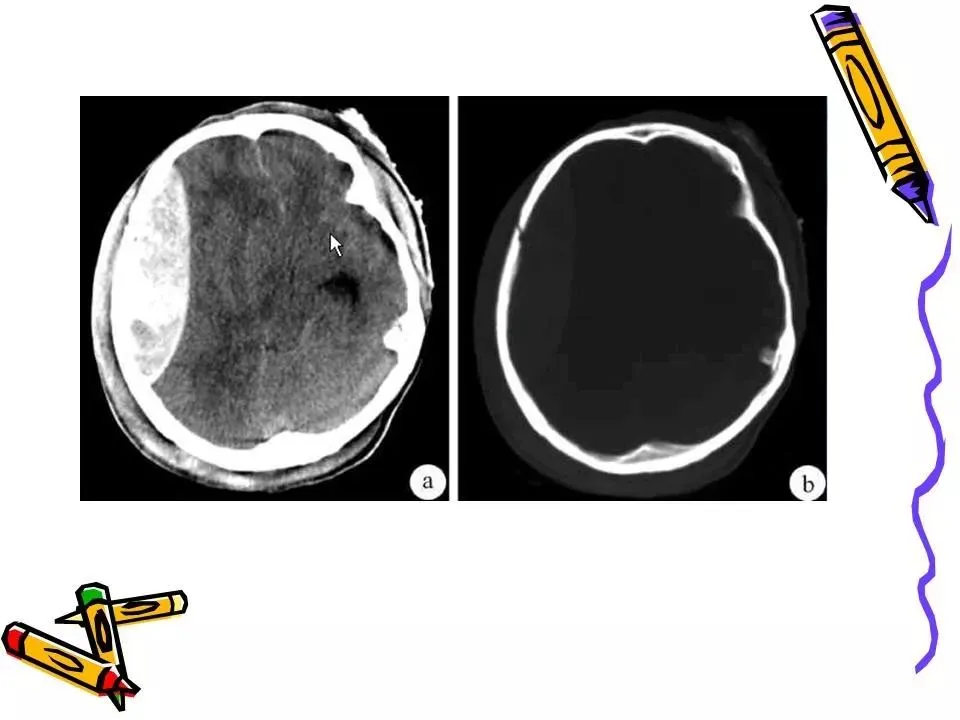

>常见颅脑外伤CT诊断(PPT)

常见颅脑外伤CT诊断(PPT)